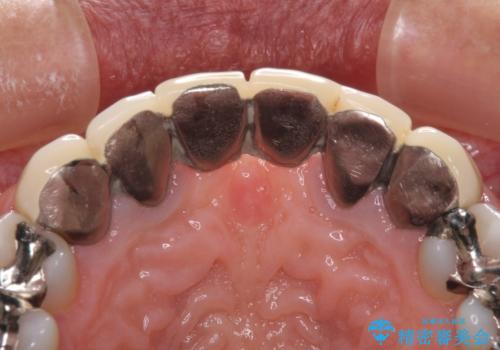

金属を使用した前歯のブリッジや奥歯の銀歯は全てオールセラミッククラウンまたはセラミックインレーとし、左下の奥歯はインプラントにより治療を行うこととしました。

遠方からの来院であったので、1回の治療時間を長めにし、できる限りの処置を集中して行うことで、来院回数を減らすことができました。